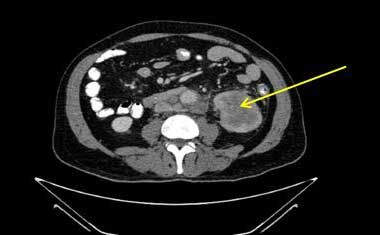

A CT scan of the abdomen of a 64-year-old man whose colorectal cancer had been diagnosed 4 years earlier revealed a new heterogeneous mass in the inferior pole of the left kidney with new bulky retroperitoneal lymphadenopathy encasing the left renal vein. Chest CT revealed multiple pulmonary nodules. Biopsies confirmed metastatic adenocarcinoma of the colon.